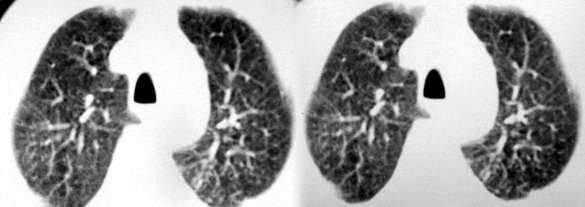

以下是引用sdqzwyx在2005-11-7 19:59:00的发言:[br]双肺弥漫大小不等的粟粒状结节影;肺纹理走行失去自然,粗细不均,边缘不规则,小叶间隔增厚;左上肺示不规则形致密影,从斑块边缘向周围伸出长短不一的致密索条影,临近的血管、支气管和叶间胸膜等结构受牵拉移位;左下肺示不规则团块状影,其内示空洞,洞内壁尚光整,左侧胸腔积液。右肺下叶背段亦示部分病灶融合。双肺可见局限性肺气肿。[br]诊断:结合病史符合三期矽肺表现(少数矽肺纤维斑块内可以形成空洞,一般认为是斑块中央感染引起坏死所致)但尘肺病人易合并肺结核,诊断可为三期+tb。所以此病人应进一步检查是否合并结核。